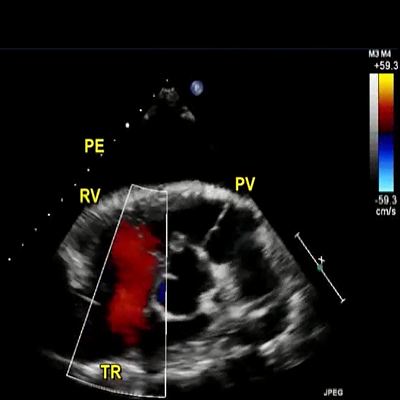

Large PE. Mild TR

915 KB